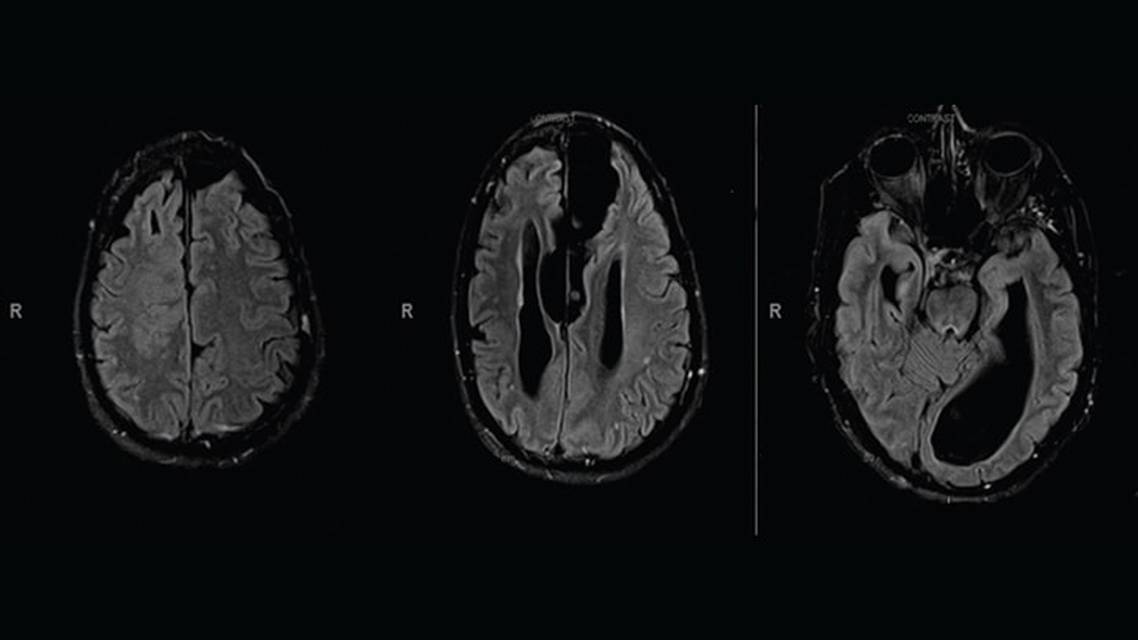

In preparation for advanced treatment with either surgery or a device, brain imaging and seizure localization with invasive EEG monitoring were obtained at age 52. MRI of the brain with and without contrast had grossly abnormal results (Figure 1), showing agenesis of the corpus callosum, arachnoid cyst, heterotopic gray matter and pachygyria of the right frontal lobe, right transmantle dysplasia, colpocephaly, and enlarged anterior commissure. Characterization of seizures during DL’s hospitalization for invasive EEG monitoring localized seizure onset to the right frontal and bitemporal head regions.